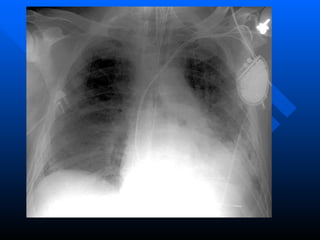

Laboratory values are generally nonspecific and primarily indicative of underlying clinical disorders. The chest radiograph usually reveals alveolar and interstitial opacities involving at least three-quarters of the lung fields  Chest computed tomography (CT) scanning in ARDS reveals extensive heterogeneity of lung involvement

Laboratory values aregenerally nonspecific and primarily indicative of underlying clinical disorders. The chest radiograph usually reveals alveolar and interstitial opacities involving at least three-quarters of the lung fields Chest computed tomography (CT) scanning in ARDS reveals extensive heterogeneity of lung involvement